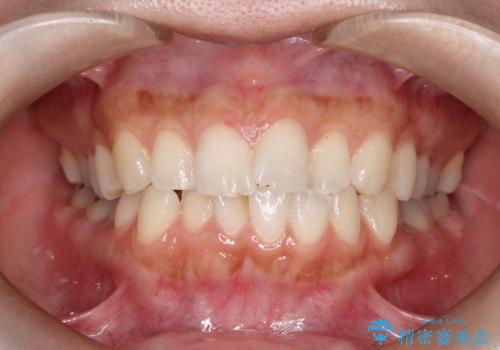

口元をさげたい ワイヤーによる抜歯矯正

- 口元が出てるのが気になるとのことで来院されました。

上下左右前から4番目の歯を抜歯して前歯を後方に下げて、口元を下げる計画としました。

口元を大きく改善したい場合は抜歯が必要となることが多いです。